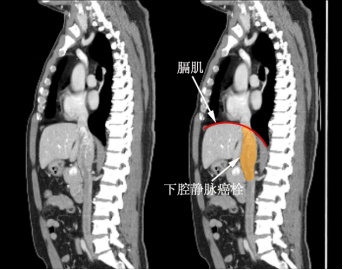

肿瘤及静脉癌栓等3D重建影像

术前增强磁共振矢状位影像